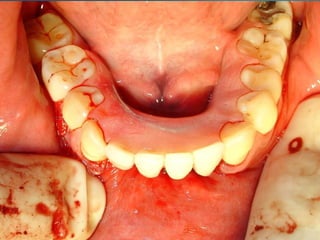

Periodontitis agresiva (de inicio precoz)

Aparece a los veinte años de edad o antes. Supone, aproximadamente, entre

un 10 y un 15% de todas las periodontitis. En la presentación clásica de la

periodontitis juvenil localizada, la pérdida ósea está localizada a los primeros

molares y a los incisivos inferiores definitivos.

Periodontitis agresiva localizada

Afecta principalmente a los primeros molares e incisivos, probablemente

porque ya están erupcionados al iniciarse la enfermedad. Puede progresar a

la forma generalizada o, posteriormente, a la periodontitis de evolución rápida.

Periodontitis de inicio precoz generalizada

Puede generarse desde una forma localizada o debutar así. Se distingue de la

periodontitis de evolución rápida en función del tiempo de inicio de la

enfermedad. Sin embargo, la edad no puede precisarse, pues el tiempo del

diagnóstico no coincide con el inicio de la enfermedad. Se relaciona con la

presencia de una serie de bacterias como son Aggregatibacter

actynomicetemcomitans o la Porfiromona gingivalis.